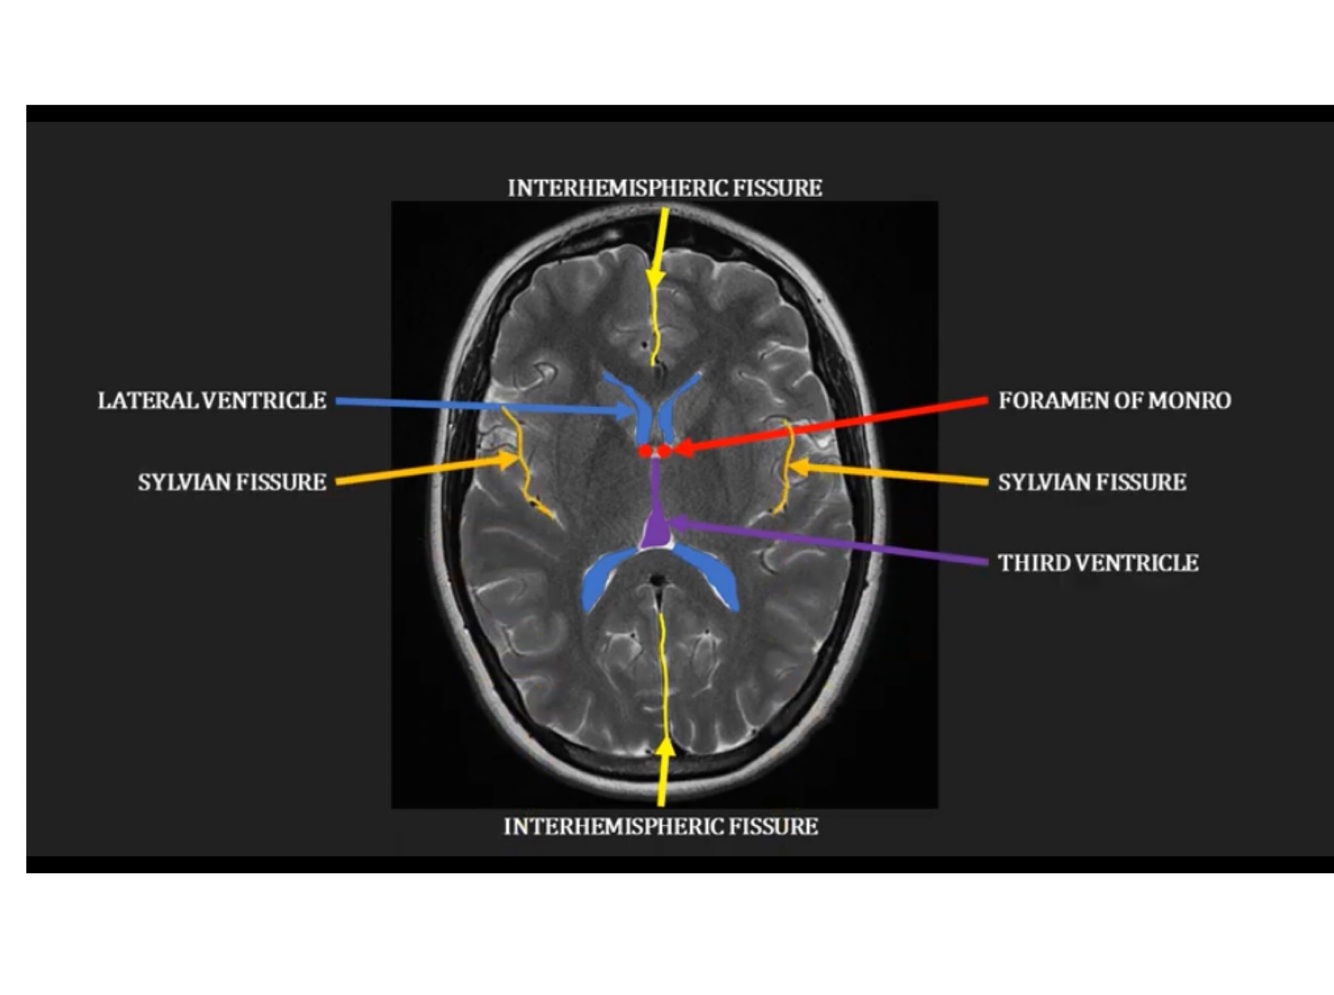

Identify the interhemispheric fissure, foramen of Monrovia, lateral ventricle, slyvian fissure

Interhemispheric fissue separates hemispheres

Lateral ventricles - paired space communicate with third ventricle via Forman of monroe,

Sylvian fissure separates the frontal and temporal lobes